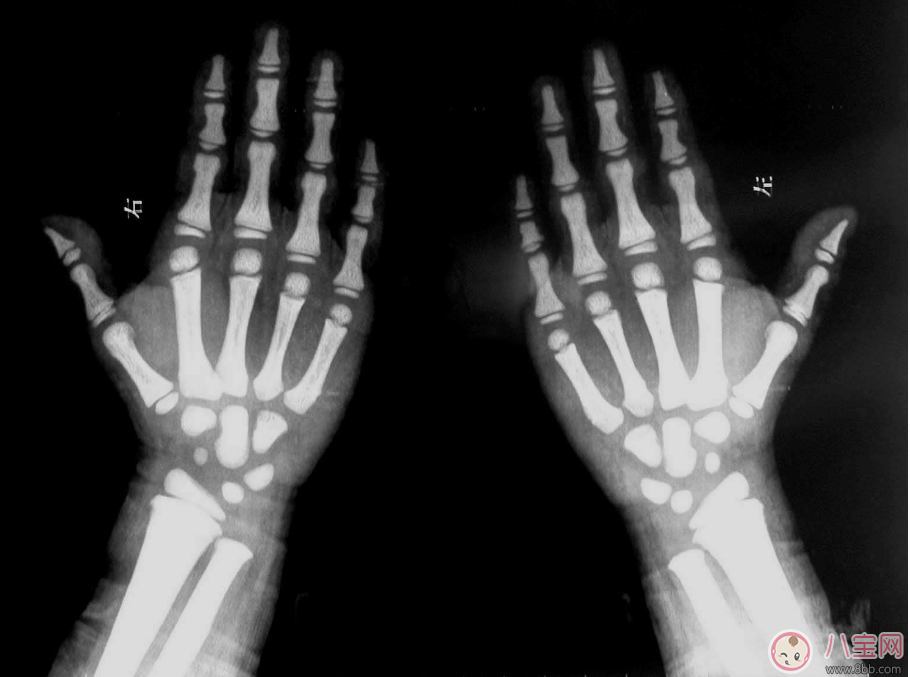

可能的诊断为A.骨髓炎B.骨结核C.石骨症D

310x389 - 35KB - JPEG